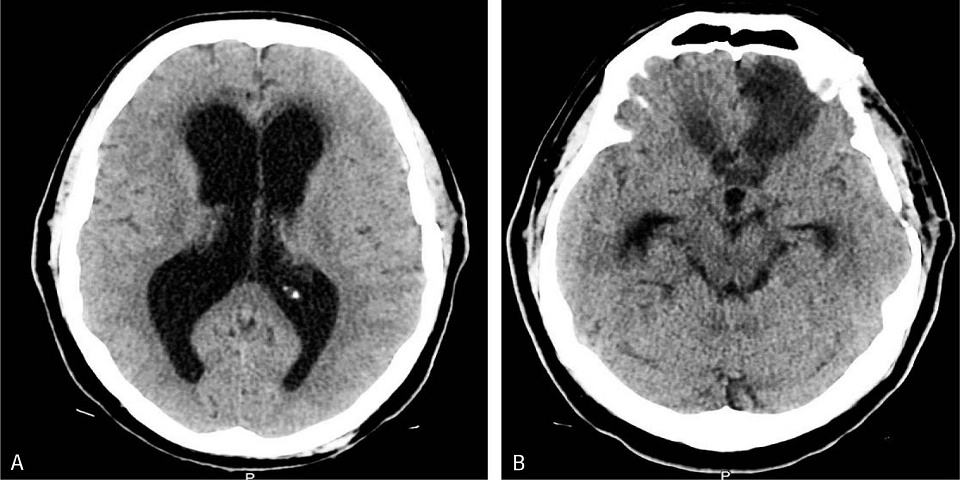

Un dispositivo implantado en el cerebro para tratar hidrocefalias carecía de autorización para emplearse en seres humanos Leer más